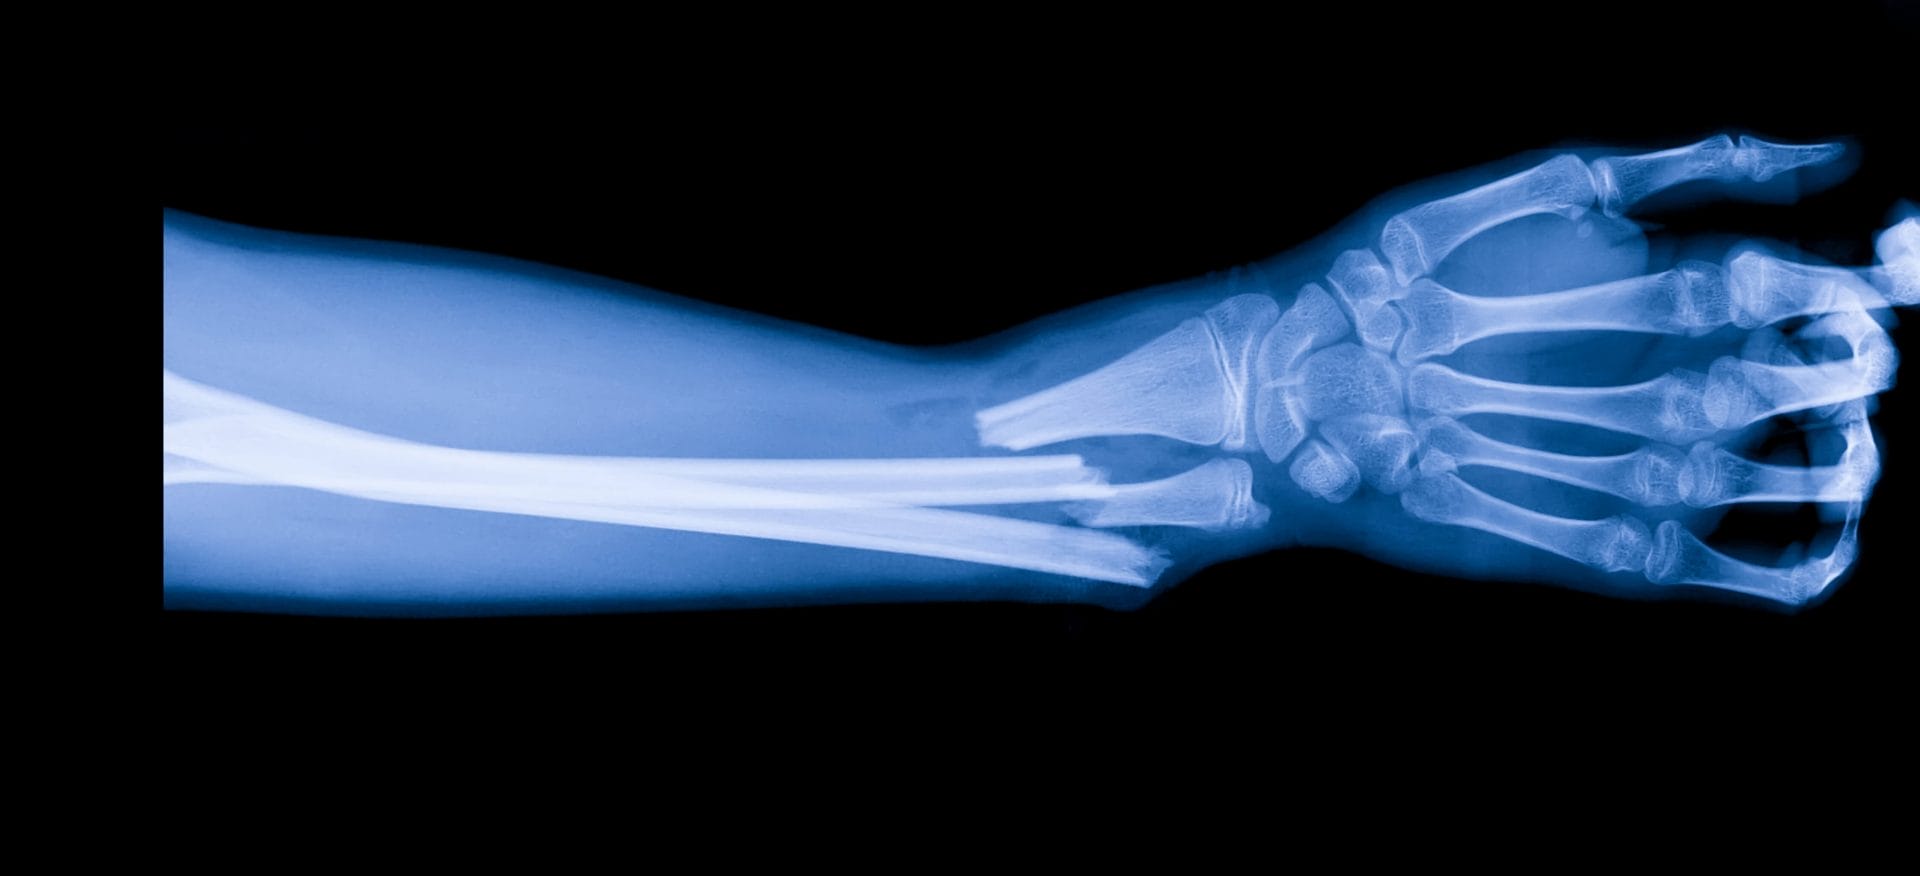

A portable 3D-printing device that applies synthetic bone grafts directly onto injuries has shown promise in animal studies, potentially cutting down the time and cost of conventional procedures.

Traditional 3D-printed bone grafts require CT scans, custom designs, and fabrication, delaying treatment. This new method allows surgeons to create and apply grafts on the spot, potentially making bone repair faster and more accessible.

While still in early stages, the handheld bone printer could transform how fractures and bone defects are treated if future trials in humans prove successful.